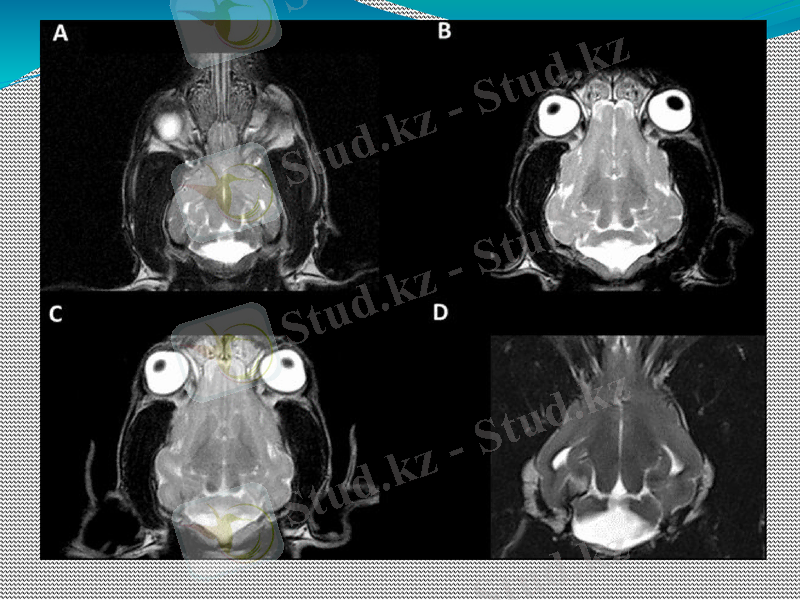

Магнитті-резонанстық бейнелеу (МРТ) нейрофизиология саласында бейнелеу техникасына жатады. Магниттік-резонанстық томограф көмегімен адам денесінің не жанурадың екіөлшемді секциялық кескіндерін рентгендік сәуле мен радиоактивті сәулелену әсерінсіз жасауға болады. Жанама әсерлері белгісіз. MRI (ағылшынша Magnetic Rezonance Imaging) аббревиатурасы магниттік-резонансты бейнелеу / ядролық спин терминімен бірдей.

МРТ қалай жұмыс істейді? Магнитті-резонанстық томография әдісі ағзадағы сутегі атомдарының магниттік қасиеттерін қолдануға мүмкіндік береді. MRI құрылғысы адамдарға көрінбейтін күшті магнит өрісін құру үшін магниттік катушканы қолданады. Нәтижесінде адам ағзасындағы сутегі атомдары біркелкі орналасқан. Қалыпты жағдайда олар кездейсоқ түрде реттеледі. Радиотолқындардан келетін жоғары жиілікті импульс сутегі атомдарының қысқа уақыт ішінде кездейсоқ реттелуін қамтамасыз етеді. Магнит өрісі салдарынан сутегі атомдары бірден өздерін біркелкі етіп туралайды. Бұл қайтару өлшенеді және сайып келгенде кескін туралы ақпарат береді.

Магнитті-резонанстық бейнелеу (МРТ)

Иттерде МРТ қай жерде орындалады?

Иттерде МРТ нені көрсете алады?